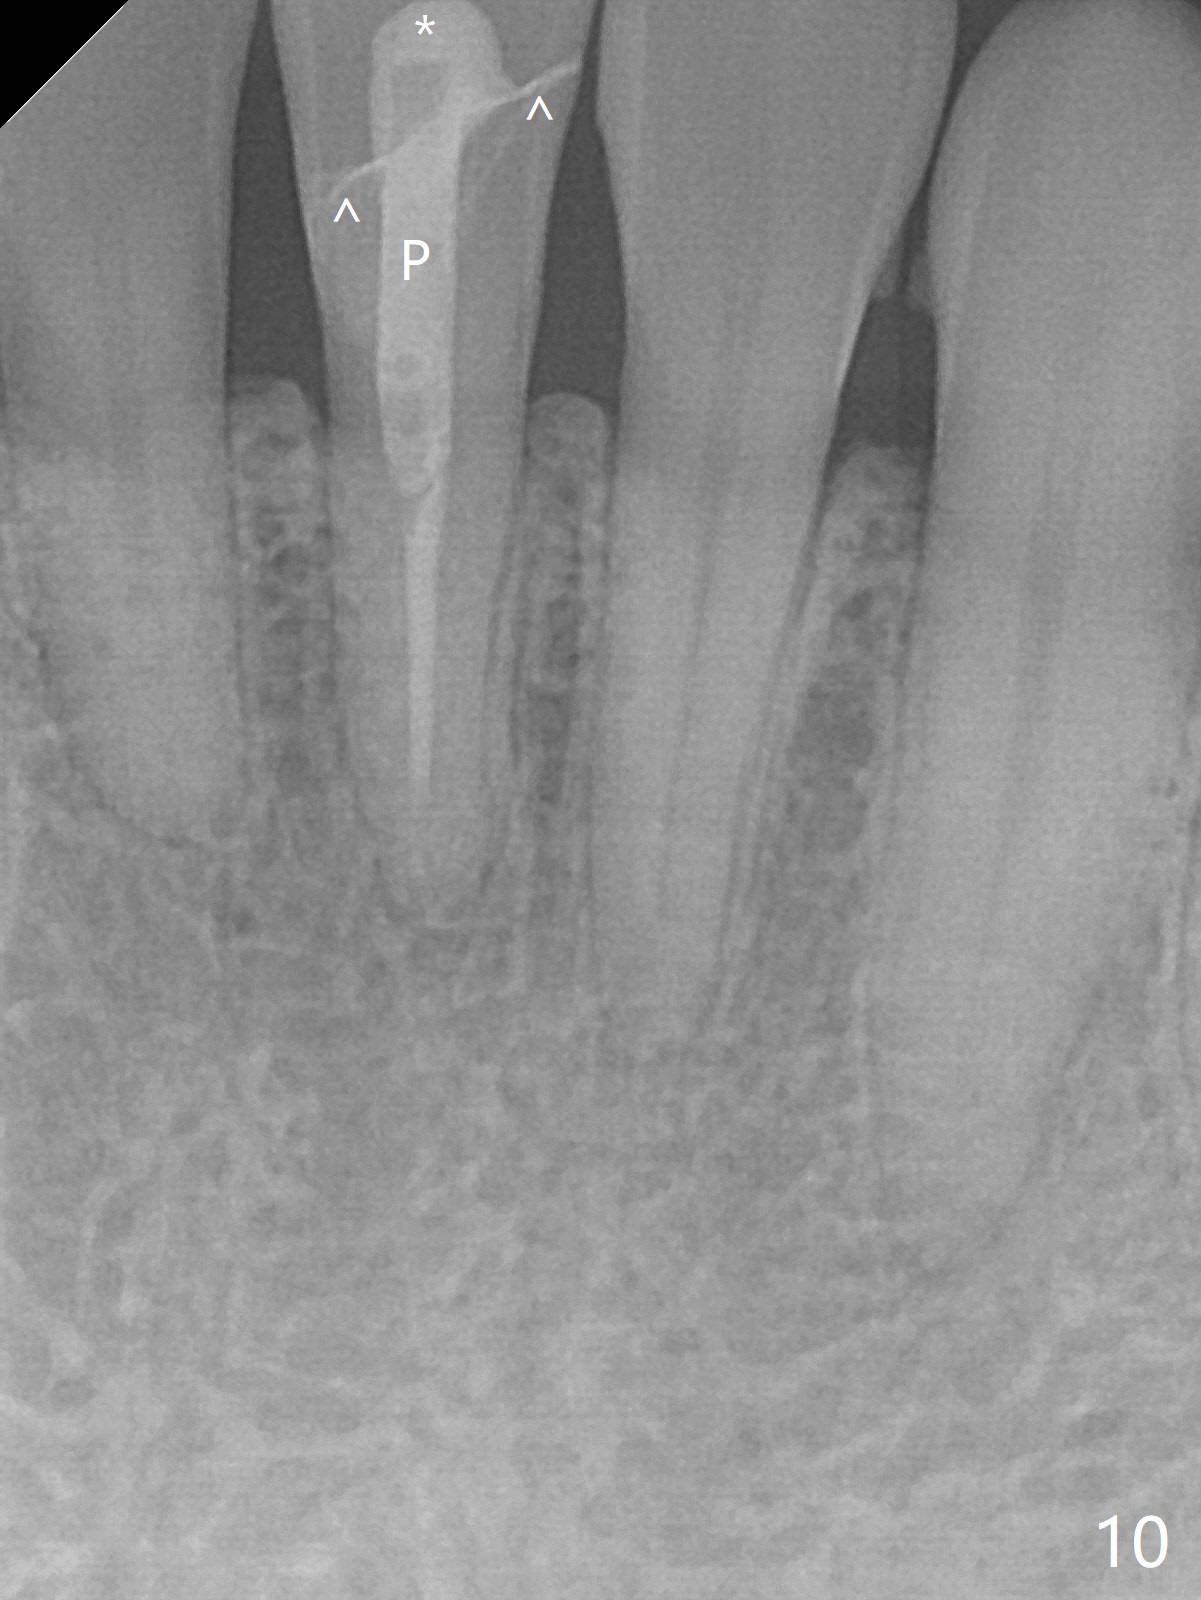

A 31-year-old woman fractured the lower left central incisor when it was hit by her 2-year-old son's head with mesiobuccal subgingival margin (Fig.1). After RCT (Fig.2), gingivectomy is conducted with eletrosurg to expose the fractured margin (Fig.3). In 2 days, a prefabricated fiber post will be bonded with the tooth and the fractured fragment together. To extend the use of the incisor, two implants are required (Fig.4). As scheduled, the patient returns with the fractured portion (Fig.5,6 (buccal (B) and lingual (L) views)). The periodontal dressing is in place (Fig.7 P). After preparation of the post space, the fiber post (Fig.10 (P)) is bonded with resin cement (Fig. 10 ^ and *) to the tooth and fragment with rubber dam (Fig.8). The patient is pleased post occlusal adjustment (Fig.9).